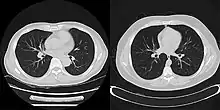

The reconstruction of an image from the acquired data is an inverse problem. Often, it is not possible to exactly solve the inverse problem directly. In this case, a direct algorithm has to approximate the solution, which might cause visible reconstruction artifacts in the image. Iterative algorithms approach the correct solution using multiple iteration steps, which allows to obtain a better reconstruction at the cost of a higher computation time.

There are a large variety of algorithms, but each starts with an assumed image, computes projections from the image, compares the original projection data and updates the image based upon the difference between the calculated and the actual projections.